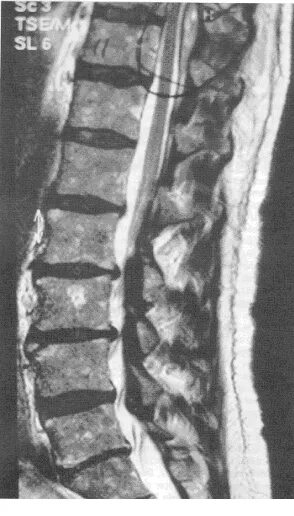

Компрессия дурального мешка что это